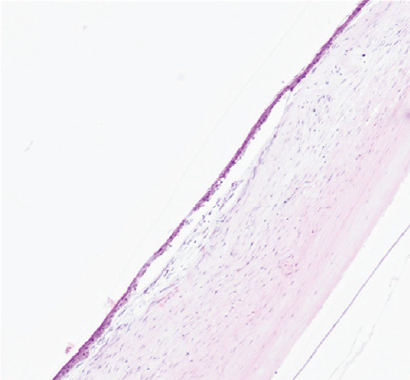

Режим 7. На данном сроке эксперимента в месте воздействия роговица имеет нехарактерный вид. Эпителий не везде прилежит к строме. Строма в области повреждения практически на 1/2 толщины образована неплотно лежащими коллагеновыми волокнами с большим числом фиброцитов и единичными лимфоцитами. Десцеметова мембрана и энодотелий остаются без изменений (рис. 5).

Рис. 5. Фрагмент роговицы после воздействия в подгруппе 1а. Фульгурация, режим 7. Окраска гематоксилином и эозином. Увеличение ×100

Fig. 5. Fragment of the cornea after exposure in subgroup 1a. Fulguration, mode 7. Stained with hematoxylin and eosin. Magnification ×100

На первом этапе эксперимента воздействие на роговицу в режиме 5 как клинически, так и гистологически выглядело недостаточным. Изменения охватывали лишь 10–15 % передней стромы. Учитывая, что в норме толщина роговицы кролика в центре составляет примерно 350 мкм, воздействию подвергались лишь около 50 мкм стромы. При воздействии в режиме 6 и 7 через 3 мес. изменения стромальной структуры распространялись примерно на 150 мкм. Воздействие в режиме 8, по нашему мнению, является избыточным. У кролика на этом режиме воздействия были самые грубые изменения в строме. Кроме того, в патологический процесс вовлекалась десцеметова мембрана.